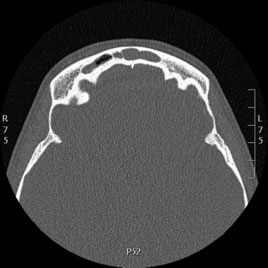

Tomografía computarizada Senos y Estructuras Nasales

Se utiliza para el estudio de los senos paranasales y diferentes estructuras de la fosa nasal.

Ejemplos